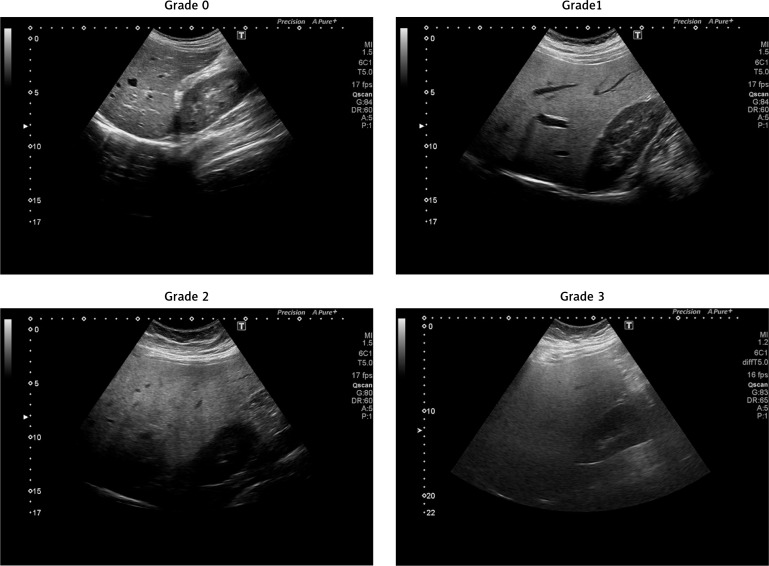

Material and methods: The analysed data were obtained from 243 individuals with NAFLD, who completed the study. Of these patients, 54 belonged to Group (1) (standard diet, SD), 104 belonged to Group (2) (wheat flour-free diet, WFFD), and 85 belonged to Group (3) (yeast-free diet, YFD). The intervention period lasted 6 months, during which participants' dietary compliance was closely monitored. Anthropometric measurements, liver function tests, and imaging studies were conducted at baseline, after 3 months, and at the endpoint.